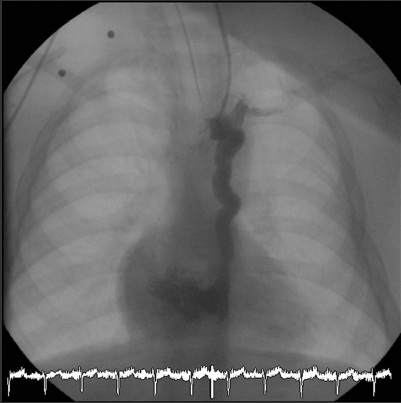

Under general anaesthesia, right heart catheterization was performed using a left internal jugular vein approach. Heparin was administered following our institutional protocol (100 IU per kilogram). A 6 French (Fr) sheath was inserted and a 5 Fr Berman catheter was used for hemodynamic assessment. Angiography showed a tortuous vessel (maximum diameter 6 mm) arising from the innominate vein and draining into the right atrium, corresponding with a left-sided superior vena cava (SVC) with high probability (Figure 1). A multipurpose catheter (MP1 4 Fr) was used to selectively cannulate the vessel and a 0.035 inch exchange wire was then positioned far into it. Over the wire, a 5 Fr guiding catheter was placed and an 8 mm Amplatzer vascular occluder (AGA Medical Corp., Plymouth, Minnesota) was deployed into the narrowest point of the vein (Figure 2A). Before releasing it, control angiography (Figure 2B) showed a significant residual shunt, and it was decided to use a larger device. A new 6 Fr guiding catheter was positioned into the vessel, and a 10 mm device was placed. An angiography performed 5 minutes later showed significant residual patency of blood flow. Thus, a 5 Fr Berman angiography catheter was positioned proximal to the plug and inflated for 10 minutes in order to interrupt the flow in the collateral vein (Figures 3A and 4). A new angiogram confirmed the absence of blood flow (Figure 3B). Subsequent control angiograms excluded the presence of other relevant collateral vessels. A significant rise in arterial blood saturation was noted (from 83% to 97%) immediately after the procedure.

Recently, excellent results in terms of safety and feasibility were reported with the Amplatzer plug occluder to close large venous vessels in patients with congenital heart disease.7,8 In our case both 8 mm and 10 mm devices were used without achieving full angiographic vascular closure 10 minutes after placement of the device. We then resorted to a technical maneuver previously reported as a useful technique in the closure of coronary fistulas,9 but to the best of our knowledge, not described before in this setting, to aid in accomplishing total occlusion of the vessel. A Berman angiographic balloon catheter was inflated proximal to the Amplatzer plug deployed and 10 minutes of additional occlusion provided by the balloon were sufficient to achieve the desired goal of complete absence of blood flow through the vessel. We believe that the venous stasis produced by the inflated balloon favored the thrombosis around the device and achieved the vascular occlusion.